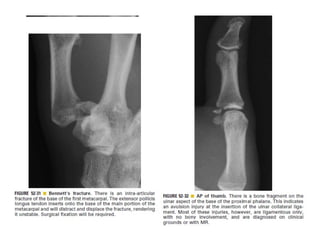

Skeletal trauma was presented by Dr Laith Fadhel with reference to Grainger's Diagnostic Radiology textbook. The presentation covered skeletal trauma as assessed through diagnostic radiology techniques. Key findings and treatments for skeletal injuries were likely discussed.